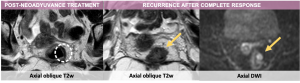

Patients with locally advanced rectal cancer typically undergo neoadjuvant chemoradiotherapy followed by surgical resection. In selected patients with complete clinical and radiological response, watch-and-wait strategy may be considered.

MRI reassessment is usually performed 6–12 weeks after neoadyuvant treatment. Expected post-treatment changes of the primary tumor includes:

- Decrease in tumor volume and extension,

- Development of low-signal fibrosis on T2-weighted images,

- Normalization of layered structure of the wall.

The tumor response is classified by MR in complete response, adequate response and poor response.

The imaging criteria for recurrence after complete response include:

- Increase in fibrotic scar depth angle >21°.

- Thickening of the fibrotic scar >10 mm (first sign of suspicion)

- New nodular areas with heterogeneous or intermediate T2 signal or diffusion restriction.